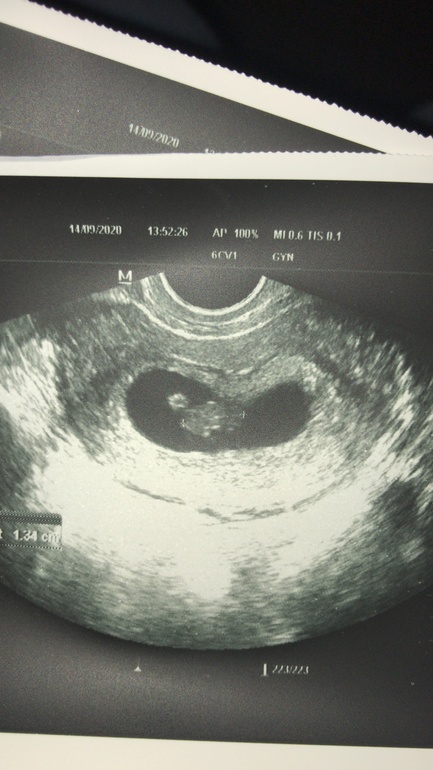

Кто разбирается в этом методе,в интернете написано по месту прикрепления хориона,а как он выглядит то

Может кто то глянет ?

Тут срок 7+4 трансвагинально

Как я поняла , если справа то девочка

Если слева то мальчик

MarinaD

Смотрят на ранних сроках, у вас уже плацента, а не хорион)))) так что ждите ещё месяц 😉

Читала что до 8 недель спокойно можно посмотреть😅

Просто самое ранние это с 5 недель где только плодное яйцо 😂

У вас уже очень чёткие края, хорион как облачко светлое вокруг яйца.